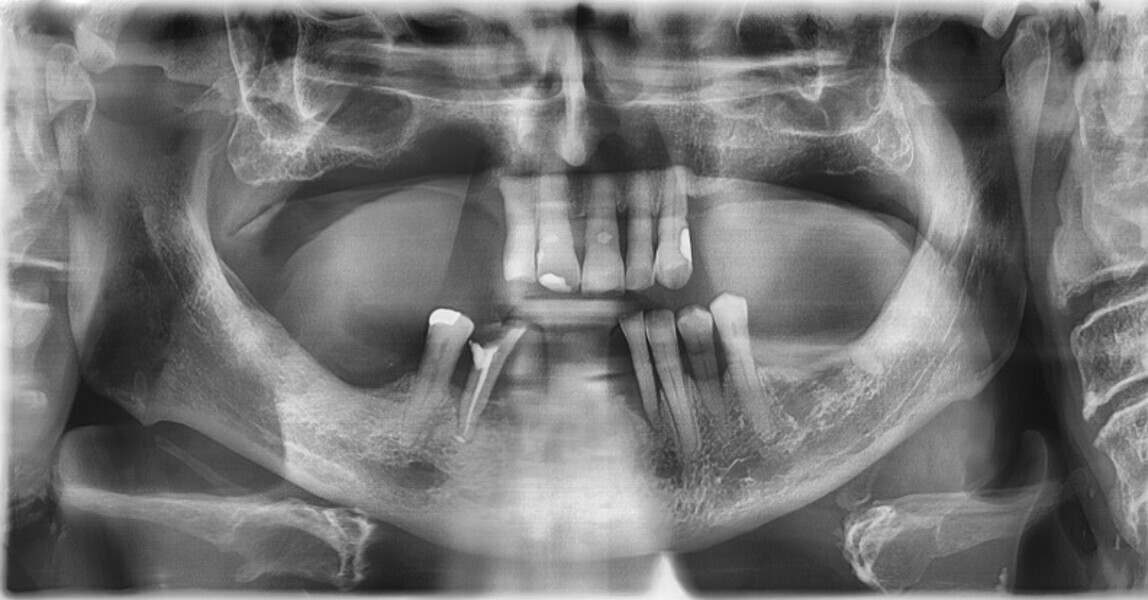

Osteonekroza występująca po zastosowaniu bisfosfonianów